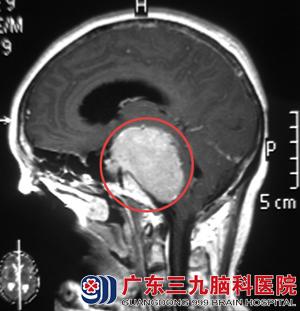

神经外五科进行了科室讨论,通过患者临床症状和影像检查,考虑脑膜瘤可能性大。完善术前检查后,由鲁明主任主刀,在全麻下行左侧岩斜区脑膜瘤切除术+基底动脉修补术+左侧脑室外引流术,镜下全切除肿瘤,手术顺利。术后病理结果为:过渡型脑膜瘤(WHO I级)。

术前